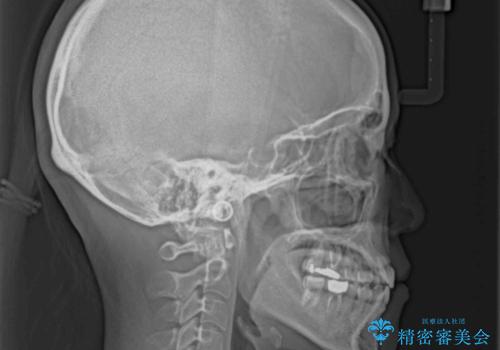

上顎骨の横幅が狭く、歯列が混み合っていたため、急速拡大装置により側方拡大し、咬み合わせと歯列を改善することとしました。

骨格的な問題を解決したことで、下顎は部分矯正で対応することができました。